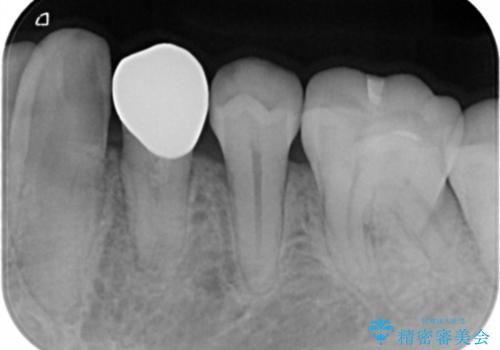

- 左下4番のう蝕を指摘され治療を希望された患者様です。

切削量などを考慮しクラウンでの治療を提案したところ、セラミックを希望されたのでフルジルコニアクラウンでの治療を選択しました。

う蝕が深かったので痛みが出る可能性をお伝えしましたが特に症状は現れなかったので、予定通りセラミッククラウンでの治療を行いました。